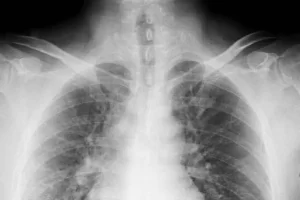

仰向けで寝られるようになり、食欲が増えて両足の冷えが治り、体力が回復した肺がん患者

彼は最初の1杯目の漢方を飲んでから、漢方の力が右肺の下まで行くのが分かるそうです。その場所が、ちょうど西洋医学の検査で分かった癌の病巣。

ほかの症状の変化は、漢方を飲んでからたくさんの痰が出て、便通はとても良くなり、今は仰向けで寝られる。食欲はたくさん増えて、両足も暖かくなり、体力もかなり回復。

彼の舌を見たら、最初両側にあった黄色くてネバネバする物が全部治りました。いろんな変化があったから、彼は慌てて再診察に来たのです。「抗がん剤を続くと、私は二度と治療しない」と私が言ったのも原因でした。

彼は今日「手の骨が痛い」と言ってました。なぜなら、骨の上に癌ができて、石みたいに硬いからです。彼はまだ状況が良くない「厥陰症」段階にあります。もし、治療して「陽明症」の症状が出れば、完全に救って来られる。